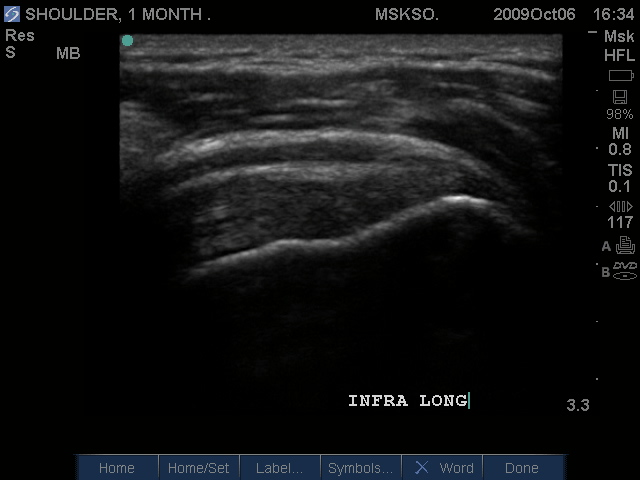

Long axis image of the Infraspinatus tendon over the posterior Greater Tuberosity also confirms bursal enlargement.

Compression shows this is not simple bursal fluid.